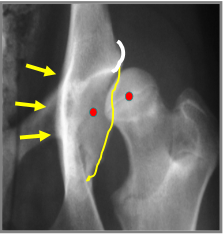

What can be seen in this image?

Red dots: show that the femoral head has subluxated they aren’t where they should be

Yellow wibbly line: remodelling changes that are trying to stabilise laxity

Yellow arrows: pointing to new bone growth/sclerosis.